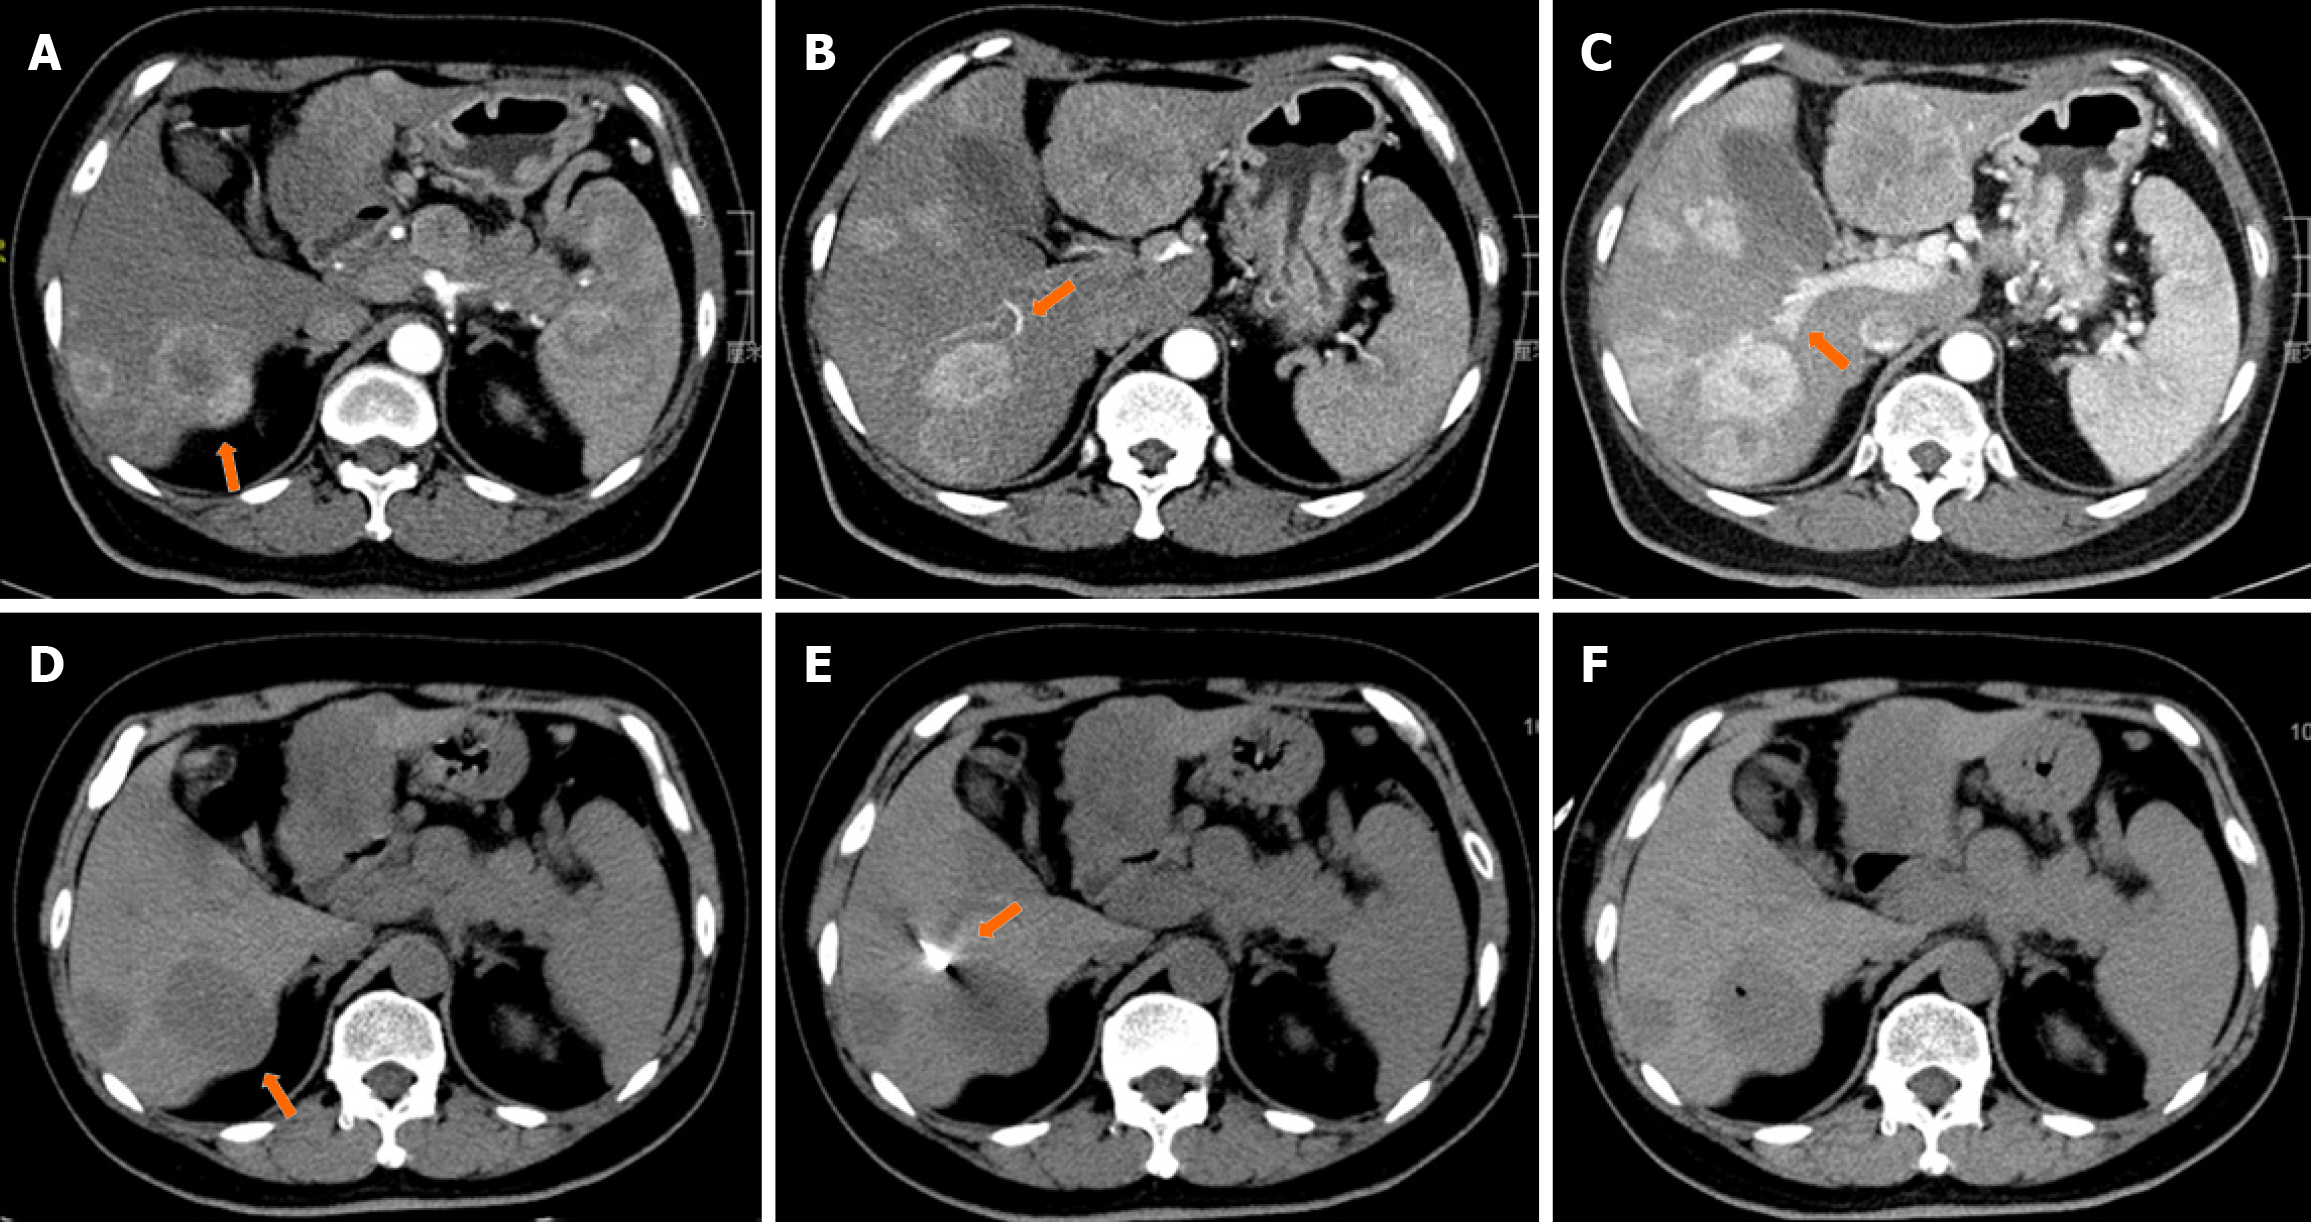

Figure 1 Computed tomography-guided biopsy of a pancreatic neuroendocrine tumor liver metastasis.

A: Axial contrast-enhanced computed tomography (CT) reveals an arterially enhancing 45 cm lesion in the right lobe of the liver (arrow); B: Axial contrast-enhanced CT reveals an artery nearby the lesion (arrow); C: Axial contrast-enhanced CT reveals a portal vein nearby the lesion (arrow); D: Procedural non-enhanced CT image at the same cross-sectional level reveals the lesion to be hypoattenuating to the liver; E: 17-gauge introducer needle (arrow) was placed in approximate location of the lesion based on the avoidance of damage to artery within the liver and portal vein; F: Post-procedural non-enhanced CT image reveals no complications.